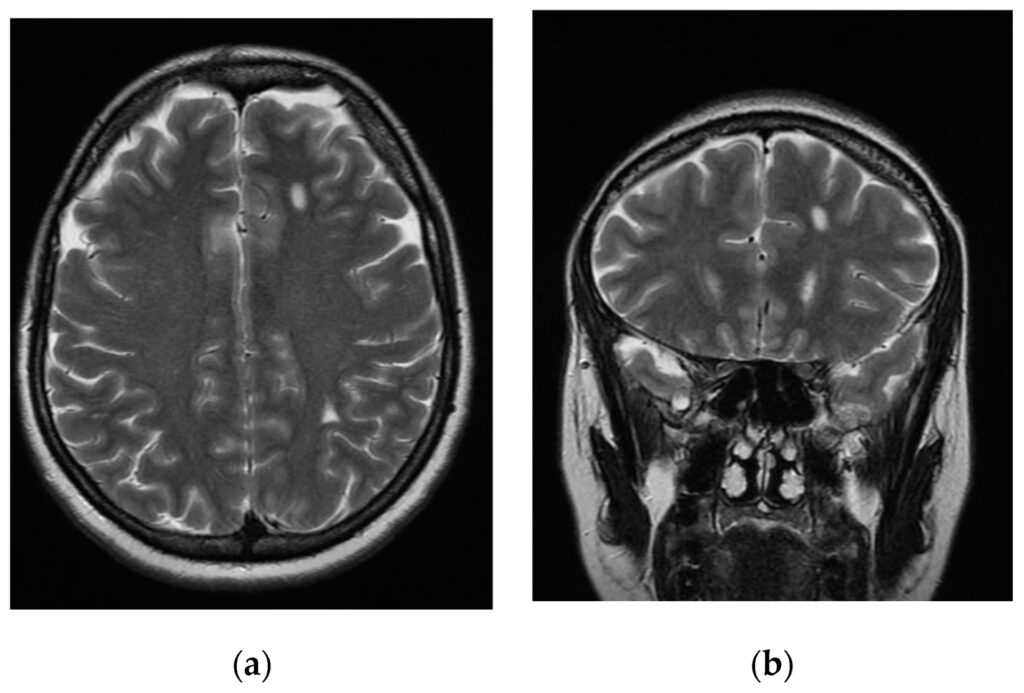

En indledende CT-scanning viste dog, at hjernekamrene ikke var forstørrede. I stedet afslørede scanningen en ukendt masse i den bagerste del af hjernen, specifikt i lillehjernen. En efterfølgende og mere detaljeret MRI-scanning viste en multiloculeret cystisk masse med tegn på tidligere blødninger. Udseendet mindede bemærkelsesværdigt meget om endometriomer (også kendt som 'chokoladecyster'), der ofte ses i bækkenet hos kvinder med endometriose. Dette var dog et højst usædvanligt fund i hjernen.

Diagnosen er ekstremt vanskelig, da tilstanden er så sjælden. Læger vil typisk starte med neurologiske undersøgelser og billeddiagnostik som CT og især MRI. MRI-scanninger er særligt gode til at vise blødt væv og kan afsløre karakteristika, der tyder på blødning i massen. Den endelige og definitive diagnose stilles dog først efter en vævsprøve (biopsi) eller kirurgisk fjernelse, hvor en patolog kan undersøge vævet under et mikroskop.